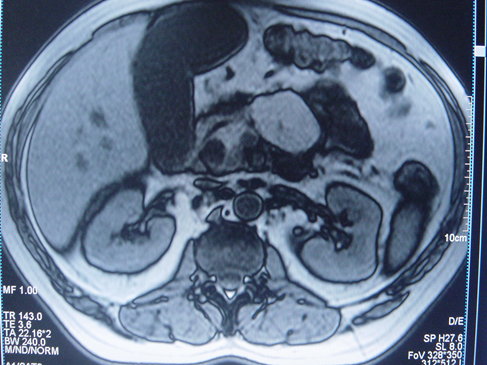

- Kontrastlı KT və ya MRT standart müayinədir, şişi və yayılma dərəcəsini müəyyənləşdirilməsində önəmlidir.

- Görüntüləmdə: erkən arterial fazada contrast tutan və venoz fazada yuyulan, MRT-də hipointens, ətraf toxumalara invaziv, böyüməyə meylli, baş nahiyyəsində yerləşərək xoledoxu və pankreatik axacağı genişləndirən (“iki axacaq simptomu”) törəmə